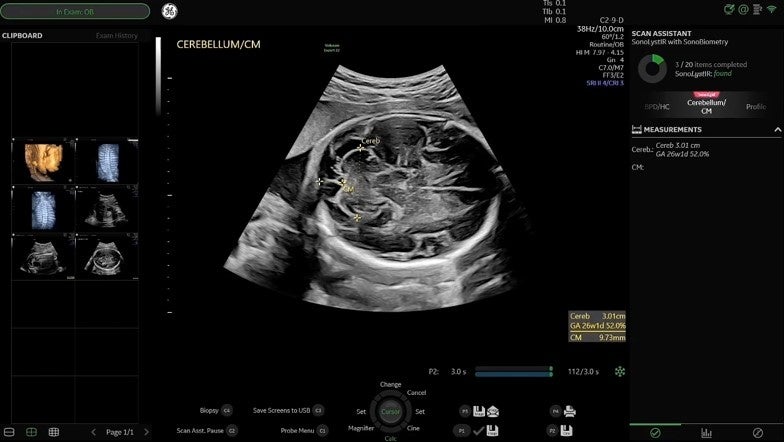

妊娠中期ISUOG(国際産婦人科超音波学会)ガイドラインに準拠したプロトコルであるSonoLystを搭載しました。ユーザがフリーズした断面を、ガイドラインの基準断面に則したどの部位であるか装置が自動認識しユーザに提案し、ユーザがそれを受け入れると、チェック済項目として保存されます。これにより、胎児スクリーニング検査のワークフロー改善とともに、取得画像のクオリティ担保や、自己学習の推進に貢献します。